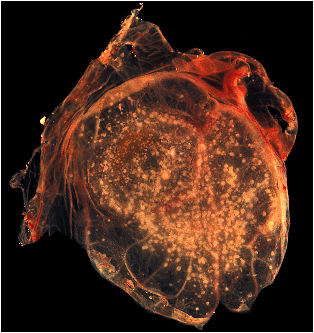

A photograph revealing smallpox virus pocks on the chorioallantoic membrane of a developing embryonic chick. Poxviruses are very easy to isolate, and will grow in a variety of cell cultures, producing characteristic hemorrhagic pocks on the chick chorioallantoic membrane (CAM). |